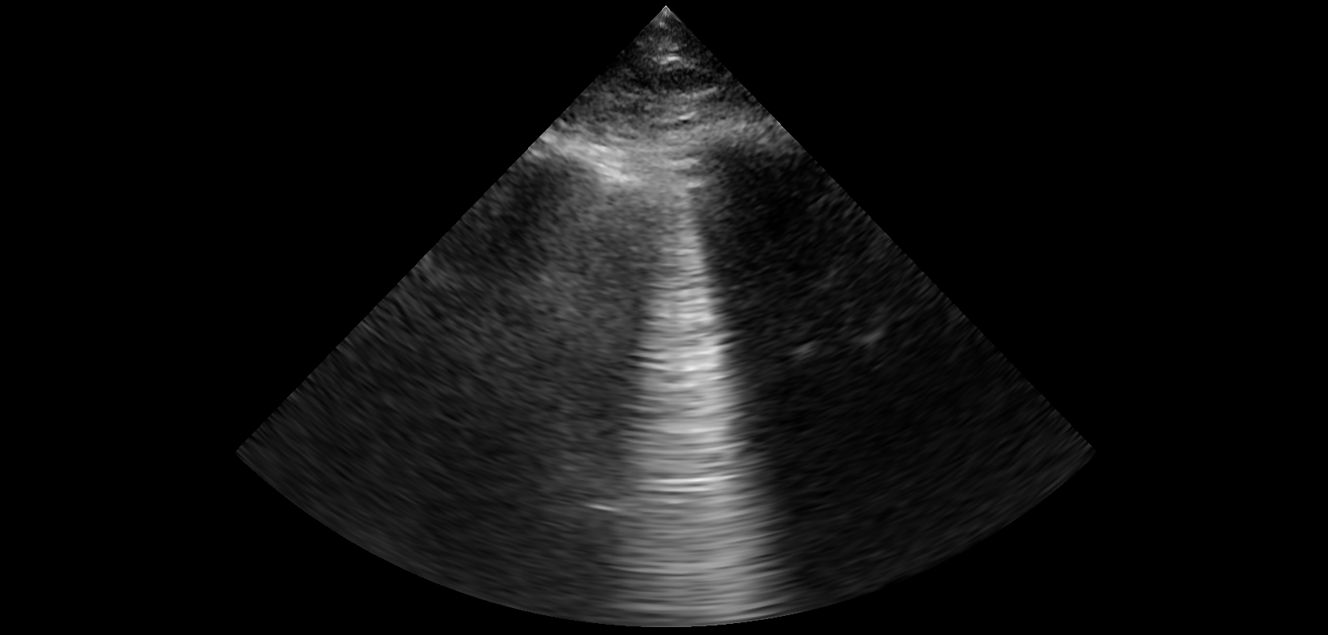

LUICA (Lungs ultrasound and IVC assessment) clinician education